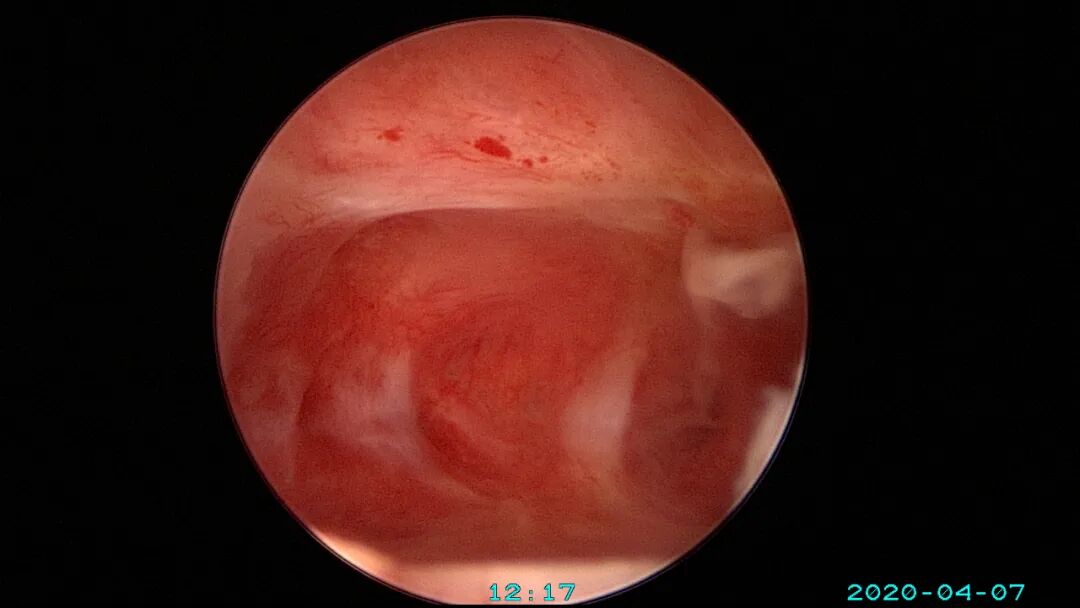

6、减少内膜损伤及输卵管开口周围损伤

个体化选择手术器械,减少内膜损伤及内膜丢失:冷刀优于能量器械,双极优于单级,电针优于电切环。能量器械设置最低有效能量,少用电凝。尽量避免探查宫深及扩宫操作,宫腔镜直视下进入宫腔,必要时采用阴道内镜方式进入,保持宫颈管及宫腔原始状态显露在宫腔镜下,不破坏病灶,便于准确诊断,精准手术。非要扩宫时,选择尖头扩宫棒,方便操作。宫颈外口狭窄或封闭时,可用尖刀片切开宫颈外口,必要时缝合牵拉宫颈再做切开,切口术后可不缝合。输卵管开口是精子和胚胎运行的重要关口,形态多样,开口周围颜色比内膜颜色浅(未被损伤的输卵管开口美兰不着色),粘膜平滑而薄,呈放射状。宫腔镜手术不要损伤输卵管开口,开口周围息肉、粘连等病变可以用微型剪、异物钳或电针处理,尽量不用电切环。宫腔镜微创理念牢记心中:手术要有助于生殖、有助于恢复月经、有助于减少粘连复发。术中保存完整手术资料,除了拍照,必要时开启摄像功能,录制手术视频,利于术后复盘手术过程,作为分析、学习、讨论、反思、提高等资料备用。

尽量保护输卵管开口周围内膜不受损伤,术中仅显露出左侧输卵管开口。该患者术后自然妊娠,34+周剖宫产分娩